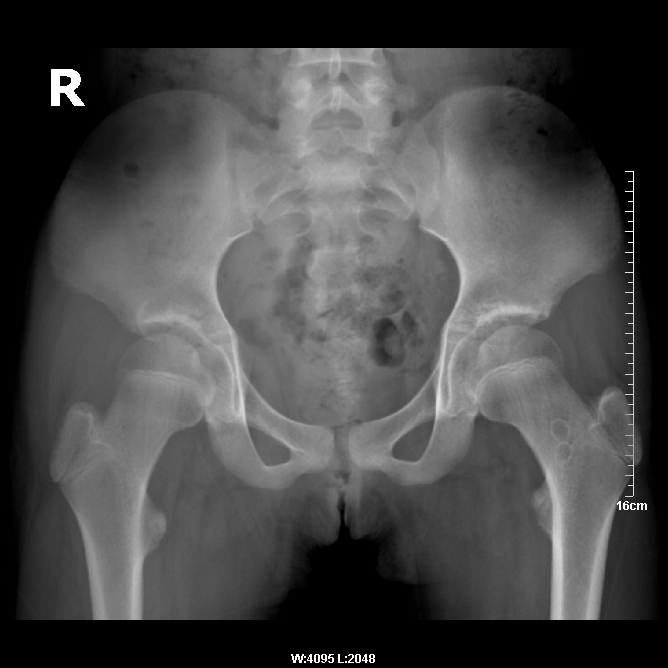

女,10岁,右髋不适3个月。拍片及ct示,股骨颈环状低密度区,边缘硬化,看看是软骨岛或股骨颈疝凹。

异常低密度囊状影在左股骨颈,而介绍病史说右髋不适......到底哪一侧?